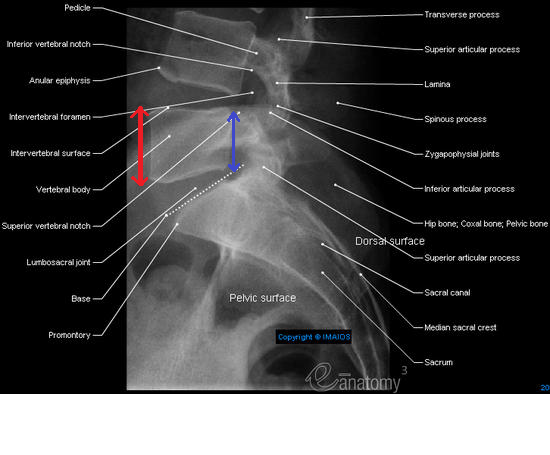

Dans la ronéo 8 p.5 il est dit que le corps de L5 est plus haut en avant qu'en arrière mais c'est pas l'inverse justement ? Je me suis demandée ça suite à plusieurs schémas comme celui là.. Merci